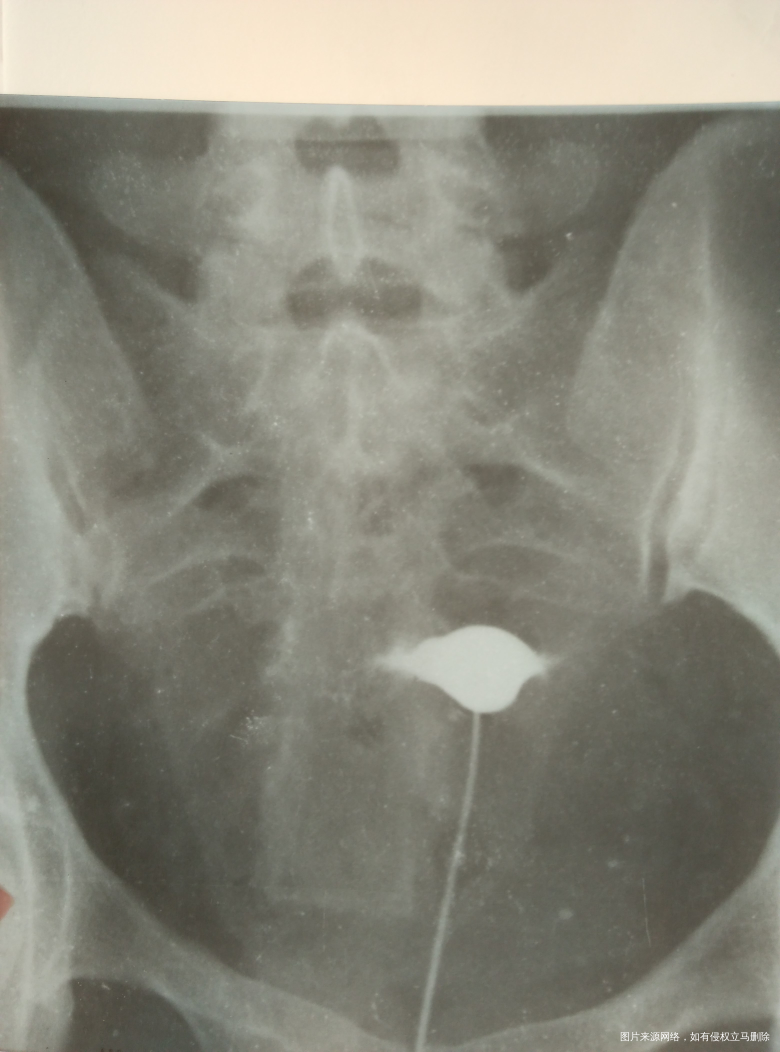

我是双侧输卵管近端堵塞,想要二胎,除了试管做手术能有多少成功率,我有青岛的社保能报销吗?大概多少费用,谢谢!